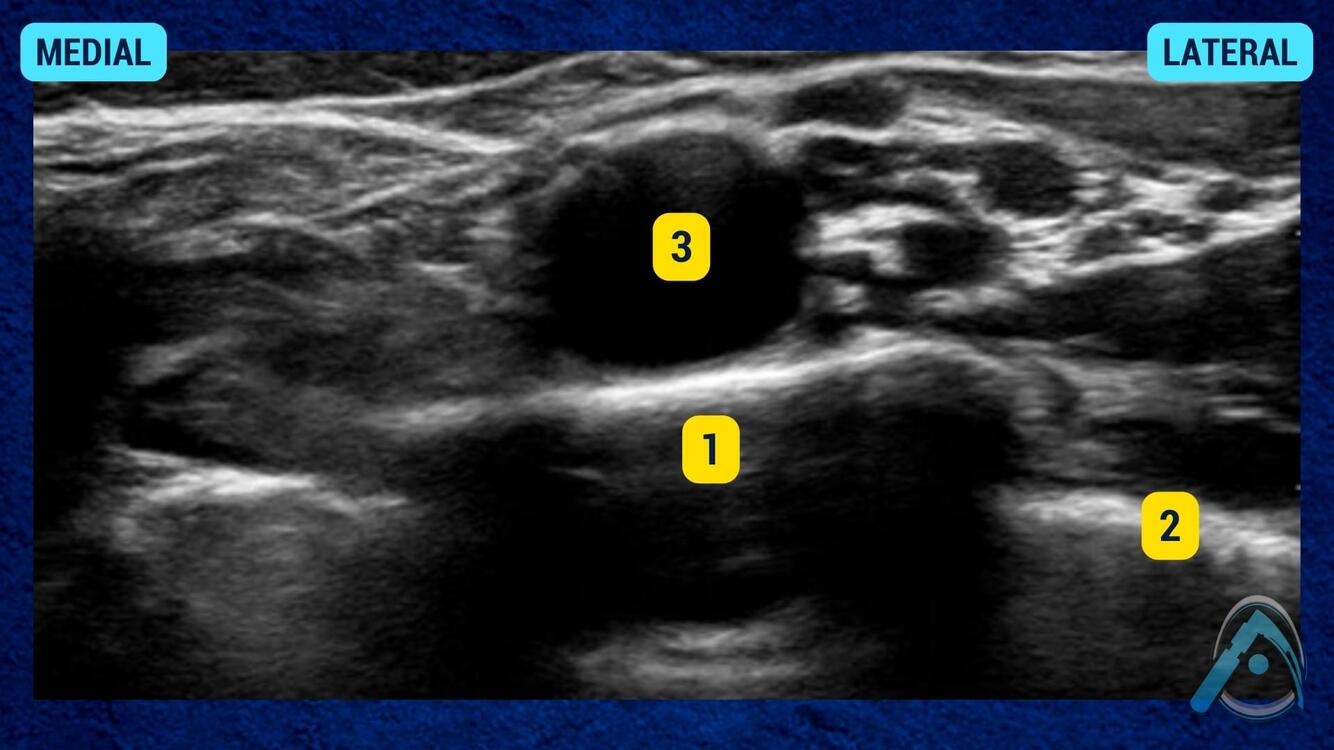

Essa janela é de um bloqueio de membro inferior para cirurgia no tornozelo. O que são as estruturas em destaque?

A

1 - artéria poplíta;

2 - nervo tibial;

3 - veia poplítea

Esse é o bloqueio do nervo ciático na fossa poplítea.